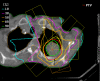

Methods: Fifty-eight patients underwent radiosurgery involving single-dose irradiation. With 25 patients, 31 metastases in the lungs were irradiated; with each of 33 patients, stage I non-small cell lung cancer (NSCLC) was subject to irradiation. The standard dose prescribed to the isocenter was 30 Gy with an axial safety margin of 10 mm and a longitudinal safety margin of 15 mm. The planning target volume (PTV) was defined using three CT scans with reference to the phases of respiration so that the movement span of the clinical target volume (CTV) was enclosed.